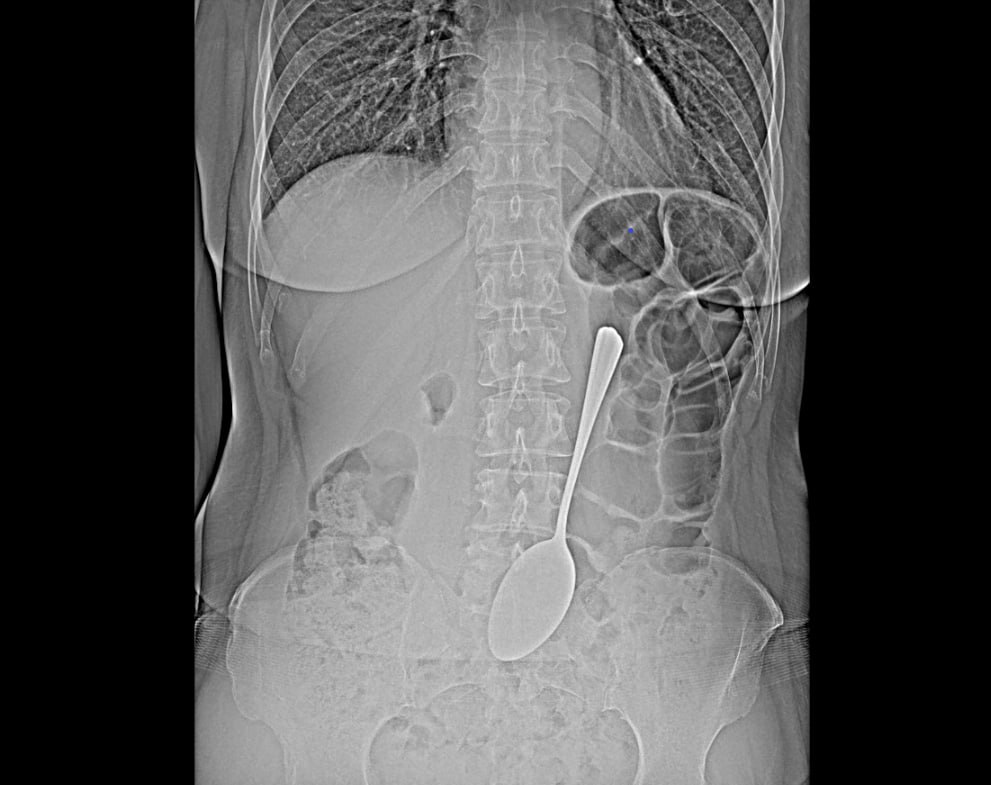

Жительница Бурятии проглотила 18-сантиметровую столовую ложку. Пациентку спасли врачи-эндоскописты БСМП имени В.В. Ангапова. Мотивы своего поступка она не объяснила.

Предмет достали из желудка с помощью эндоскопа и соответствующих инструментов. Это помогло избежать сложной хирургической операции. После женщину отпустили.

«Инородные предметы в желудке могут спровоцировать перфорацию желудка, кишечную непроходимость. Если мелкие предметы вроде монет могут выйти из организма самостоятельно, то в случае со столовой ложкой все могло быть серьезнее», - прокомментировала врач-эндоскопист РК БСМП Валентина Бабудоржиева.